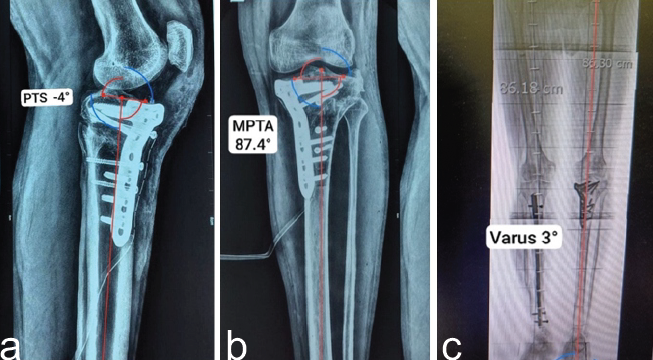

Under fluoroscopic control, the medial side was opened more to achieve the desired coronal plane correction based on pre-operative planning. To maintain the created gap, wedge-shaped tricortical autografts harvested from the iliac crest. Graft was prepared in differential manner and inserted accordingly to correct varus along with slope. A 17-mm-thick graft was placed on the medial side to provide medial column support, while a 12-mm-thick graft was positioned laterally. A central block of 14 mm thickness was interposed between the two to stabilize the construct (Fig. 5a). The osteotomy was stabilized using a high tibial osteotomy (HTO) plate (Fig. 5b). Finally, the previously elevated tibial tubercle was reattached using a cancellous screw, ensuring restoration of appropriate patellar height and alignment and avoiding patella baja (Fig. 5b). Fixation of tibial tuberosity itself acts as a biological plate providing stability to osteotomy site.

Figure 5: (a) Insertion of differential thickness bone graft to correct varus and hyperextension both simultaneously and (b) a Tomofix HTO plate is fixed under fluoroscopic guidance, just medial to tibial tuberosity osteotomy line, along with fixation of tibial tuberosity with 3 CC screw as “biological plate.”

Post-operative course and follow-up

On post-operative radiograph, there is marked correction of deformity in both planes with residual varus of mere 3° with MPTA-87.4°, whereas tibial slope was restored up to −4° (Fig. 6a, b, c).

Figure 6: (a) Post-operative anteroposterior radiograph showing restored MPTA 87.4° after valgus osteotomy demonstrating correction (10.5°) from 76.9°, (b) post-operative lateral radiograph showing correction of posterior (reversed) tibial slope from −30° to −4°, and (c) post-operative scanogram illustrating residual post-operative varus of merely 3° making it like normal opposite limb (constitutional varus).